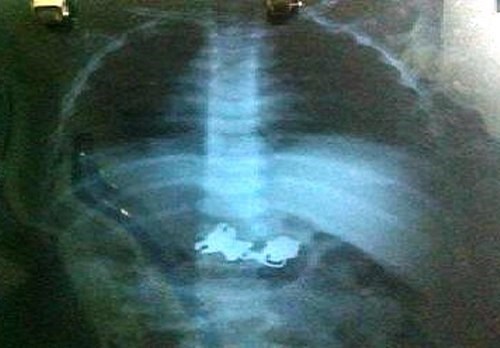

Ngày 17/10, bác sĩ Nguyễn Đức Phước-giám đốc Bệnh viện Đa khoa huyện Trảng Bom (Đồng Nai) cho biết bệnh viện vừa siêu âm phát hiện một phụ nữ mang 4 bào thai.